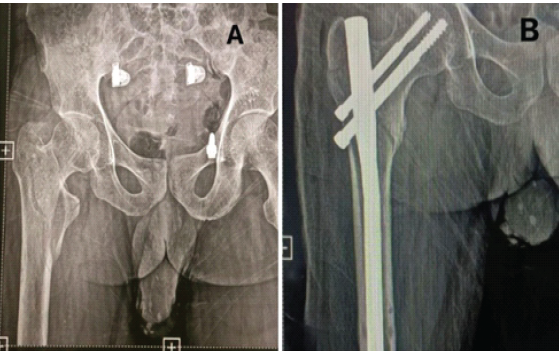

A 55-year-old male patient with TYPE 31-A2.1 pertrochanteric femur fracture of the right side (Fig. 2).

Figure 2: (a) Pre-operative anterior-posterior (A-P) view X-ray showing TYPE 31-A2.1 pertrochanteric femur fracture of the right side. (b) Post-operative A-P view X-ray showing pertrochanteric femur fracture fixed with long proximal femur nail.